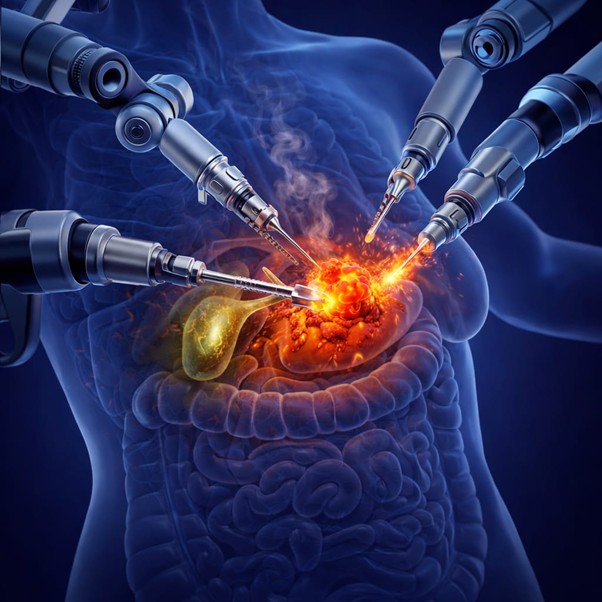

Introduction Minimally Invasive Cancer Surgery in Mira Road. Let’s understand, Cancer treatment has evolved dramatically over the past few decades, with surgical…

Why Choose Laparoscopic Cancer Surgery in Mira Road for Cancer Treatment Cancer treatment has evolved significantly over the past few decades, with…